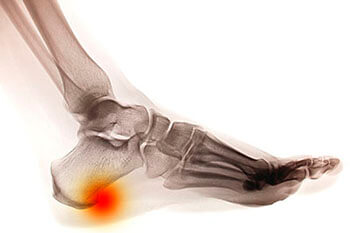

Heel Spurs are boney protrusions that develop on the bottom edge of the heel bone when it sustains repeated stress and the body sends calcium to the area in response. This extra calcium builds up over time to form sharp outgrowths on the bone that can sometimes reach 1/2” in length.

Heel spurs are often asymptomatic and are only discovered on an X-ray. If they are symptomatic, they can cause intermittent or chronic pain, inflammation, and tenderness at the bottom of the heel.